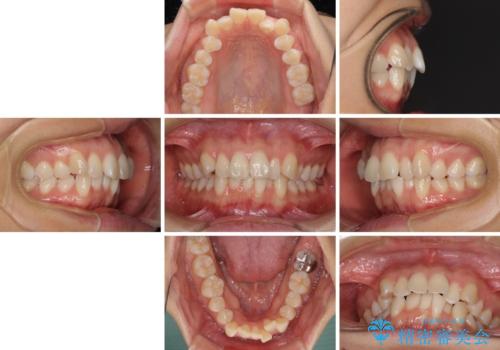

前歯のデコボコを抜歯矯正で改善 メタル装置で費用を抑える

- 前歯のデコボコと口元の突出感を気にして来院された患者様です。

非抜歯矯正ではデコボコを解消することでより口元が突出してしまうため、上下左右の小臼歯4本の抜歯を行い、ワイヤー装置による矯正治療を行うこととしました。